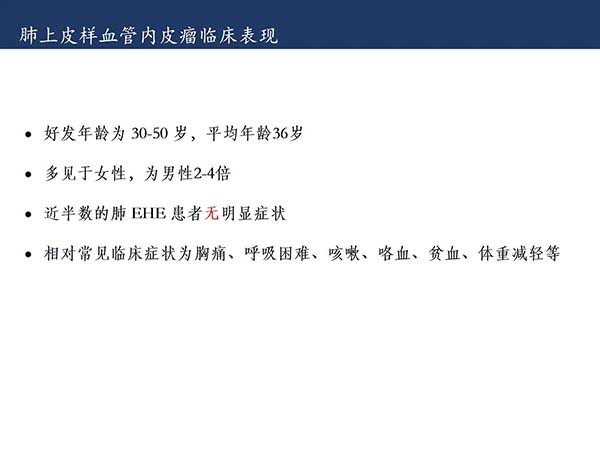

【杨柳科普】肺上皮样血管内皮瘤的影像表现